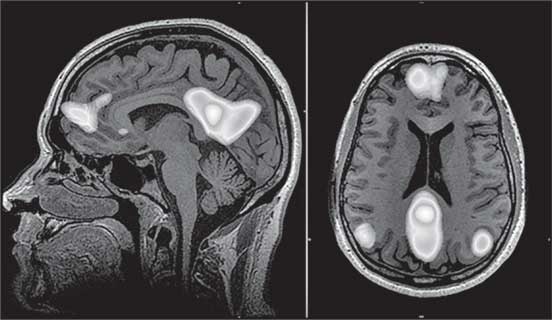

Иллюстрация к книге — Мозг. Как он устроен и что с ним делать [i_040.jpg]

Рис. 40. Структуры дефолт-системы мозга (выделены светлым)

Вероятно, эта система, называемая также сетью пассивного режима работы мозга (СПРРМ), сформировалась в нашем далеком эволюционном прошлом, когда мы еще были стайными.